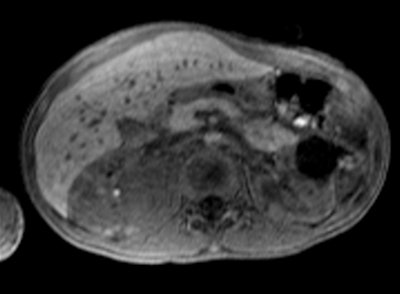

Siemens is also touting several HELX Evolution features: Virtual Touch imaging (VTi), Virtual Touch quantification (VTq), Virtual Touch IQ (VTIQ), and eSie Touch elasticity imaging, designed to visualize and measure tissue stiffness so clinicians can better evaluate anatomy.

Tissue strain analysis of a thyroid lesion using Virtual Touch IQ. Image courtesy of Siemens.VTIQ is based on Siemens' acoustic radiation force impulse (ARFI) technology, and physicians can quantifiably assess the stiffness of tissue in small parts, such as the breast and thyroid. Numerical values are shown simultaneously against a qualitative color map over the user-defined region of interest for greater detail of abnormalities within tissue.

Previously available exclusively on the Acuson S3000 system, VTIQ is now offered on the Acuson S2000 HELX Evolution model as well.

VTi and VTIQ are currently available, whereas VTq is pending FDA clearance.